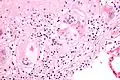

Asteroid body

Two asteroid bodies. H&E stain.

An asteroid body is a microscopic finding seen within the giant cells of granulomas in diseases such as sarcoidosis and foreign-body giant cell reactions.[1]